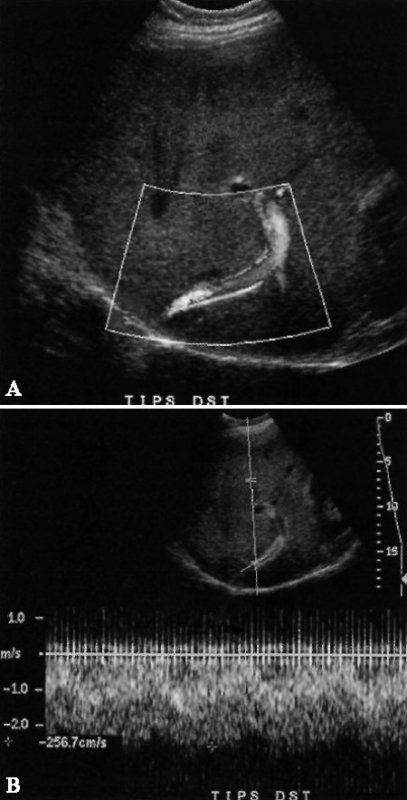

Чаще всего участок сужения обнаруживают в дистальном отделе печеночной вены, как правило, внутри шунта (фото 15).

Фото 15. Стеноз TIPS. А – цветовая допплерограмма демонстрирует увеличение скорости потока в дистальном конце шунта, о чем свидетельствует смешивание цветов. В – спектральная допплерография показала очаговый дистальный стеноз шунта, скорость потока в котором составила 256,7 см/с